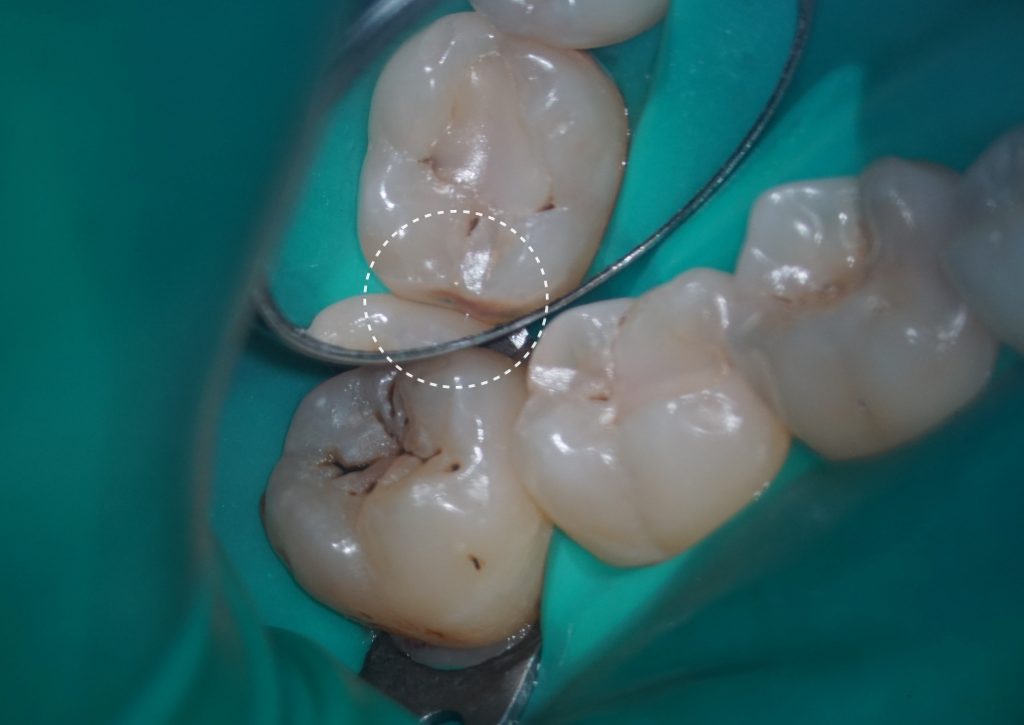

Клинически подтверждено наличие кариеса на дистальной и мезиальной поверхностях зуба 4.7